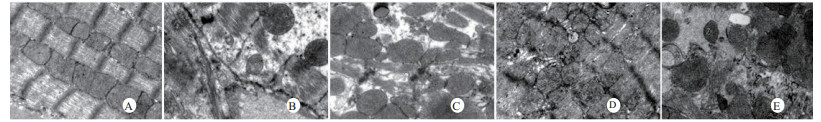

光镜下可见,假手术组肺泡大小形态均匀,结构清晰,肺泡腔内无出血和白细胞浸润;感染性休克组肺泡壁破坏严重,血管壁和肺泡间隔明显增厚;U50488H+感染性休克组大部分肺泡腔均匀一致,肺间隔略增厚,肺泡壁轻度水肿,但出血和白细胞浸润情况比感染性休克组明显减轻(图 1)。假手术组心肌细胞大小一致,排列整齐,核浆比正常,心肌细胞核呈椭圆型,胞浆均匀红染;感染性休克组心肌细胞肿胀,体积明显增大,细胞核大而异型,核内染色质固缩、边集,白细胞浸润明显增加;U50488H+感染性休克组多数心肌细胞形态相对正常,少数心肌细胞呈现脂肪变性(图 2)。假手术组肝细胞结构完整,肝小叶形态正常;感染性休克组肝细胞显著肿胀、呈空泡样和点状/小片状坏死;U50488H+感染性休克组肝细胞轻度肿胀,未见明显坏死灶、肝血窦扩张和炎性细胞浸润(图 3)。假手术组肾组织结构大致正常;感染性休克组肾小管细胞轻度水肿、空泡变性;U50488H+感染性休克组肾小管形态大致正常,间质无明显出血水肿(图 4)。

| A:假手术组,B:感染性休克组,C:U50488H+感染性休克组,D:nor-BNI+U50488H+感染性休克组,E:nor-BNI+感染性休克组 图 1 各组光镜下肺组织病理学改变(HE×400) Fig 1 Histopathological features of lung(HE×400) |

扫描电镜下可见,假手术组肺泡形态完整,肺泡壁光滑;感染性休克组肺泡明显压缩畸形,肺泡隔肿胀、扭曲、隆起;U50488H+感染性休克组肺泡形态大致完整,少数肺泡壁肿胀受损(图 5)。透射电镜下可见,假手术组心肌细胞形态正常;感染性休克组心肌细胞溶解、坏死、肌纤维断裂;U50488H+感染性休克组心肌细胞大致正常,无明显坏死(图 6)。假手术组肝细胞形态正常,毛细胆管未见扩张;感染性休克组肝细胞大片坏死,毛细胆管明显扩张;U50488H+感染性休克组肝细胞形态大致正常,毛细胆管略扩张(图 7)。假手术组肾小管上皮细胞形态狭长,核卵圆形,位于基底部;感染性休克组肾小管上皮断裂,微绒毛缺失;U50488H+感染性休克组肾小管上皮细胞大致正常,微绒毛不平滑,但无明显坏死(图 8)。

| A:假手术组,B:感染性休克组,C:U50488H+感染性休克组,D:nor-BNI+U50488H+感染性休克组,E:nor-BNI+感染性休克组 图 5 肺组织扫描电镜观察(×200) Fig 5 Scanning electronic microscopic photos of lung(×200) |

本研究还进一步观察了感染性休克大鼠重要脏器的病理学变化与超微结构。结果发现,感染性休克时,肺泡壁破坏严重,血管壁和肺泡间隔明显增厚,炎症细胞浸润较多,肺泡明显压缩畸形,肺泡隔肿胀,扭曲,隆起。该结果与潘景业等的报道一致。同时实验发现,U50488H可减轻感染性休克肺泡壁出血水肿与肺组织炎性细胞浸润,抑制肺间隔增厚。实验还观察到感染性休克大鼠心肌纤维肿胀、扭曲、断裂、溶解,并由此导致心功能障碍。U50488H亦可减轻线粒体肿胀崩解和心肌细胞溶解与坏死,可能与U50488H减轻心肌抑制有关[12],具体机制与分子通路尚需进一步实验验证。本研究还观察到感染性休克大鼠肝细胞出现肿胀、空泡样脂肪变性和点状/小片状坏死,毛细胆管明显增多、扩张;肾小管细胞轻度水肿、空泡变性,肾小管上皮细胞微绒毛缺失,细胞崩解,肾小管上皮断裂。预先给予U50488H可显著减轻感染性休克肝细胞浊肿、肝血窦扩张和炎性细胞浸润;抑制肾小管上皮细胞核变形、微绒毛坏死和间质出血水肿。nor-BNI可阻断这一效应。上述结果均提示U50488H可通过激动κ-阿片受体,改善肝脏和肾脏血流量保护感染性休克肝脏和肾脏功能,具体机制可能和细胞凋亡等相关。